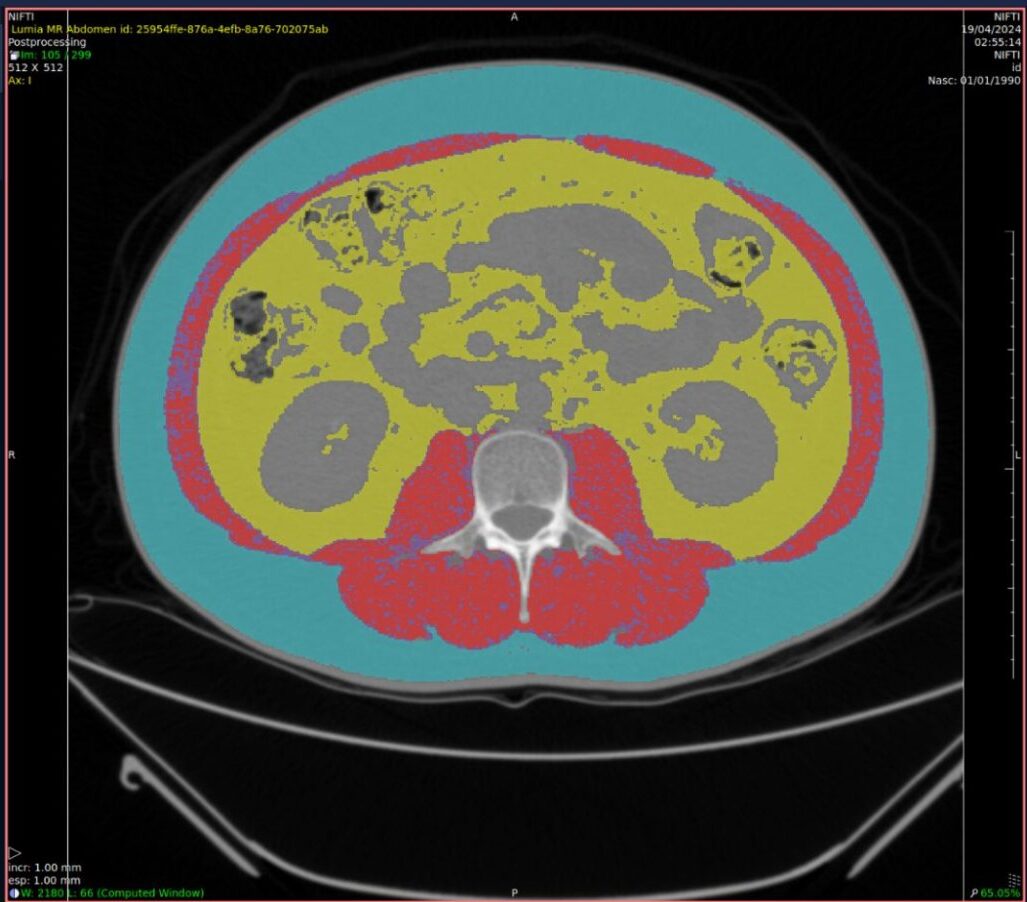

IA para cálculo de sarcopenia

Classifica-se como sarcopenia a alteração da musculatura esquelética caracterizada pela redução da força e da massa muscular secundária ao envelhecimento, que compromete o desempenho físico do indivíduo.

Ferramentas de IA com essa especialidade podem sinalizar achados clínicos e realizar uma medição automatizada da distribuição de gordura abdominal acompanhada de avaliação da massa muscular.